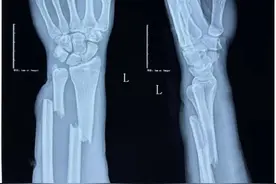

18岁的王同学是一名高三体育特长生,为冲刺心仪院校,每天都要进行高强度训练。然而,今年1月底,距离体考不到100天时,王同学却在训练中意外摔倒,导致左前臂严重骨折。检查结果显示,王同学左前臂桡尺骨骨干短缩畸形移位,当地医院建议手术治疗。